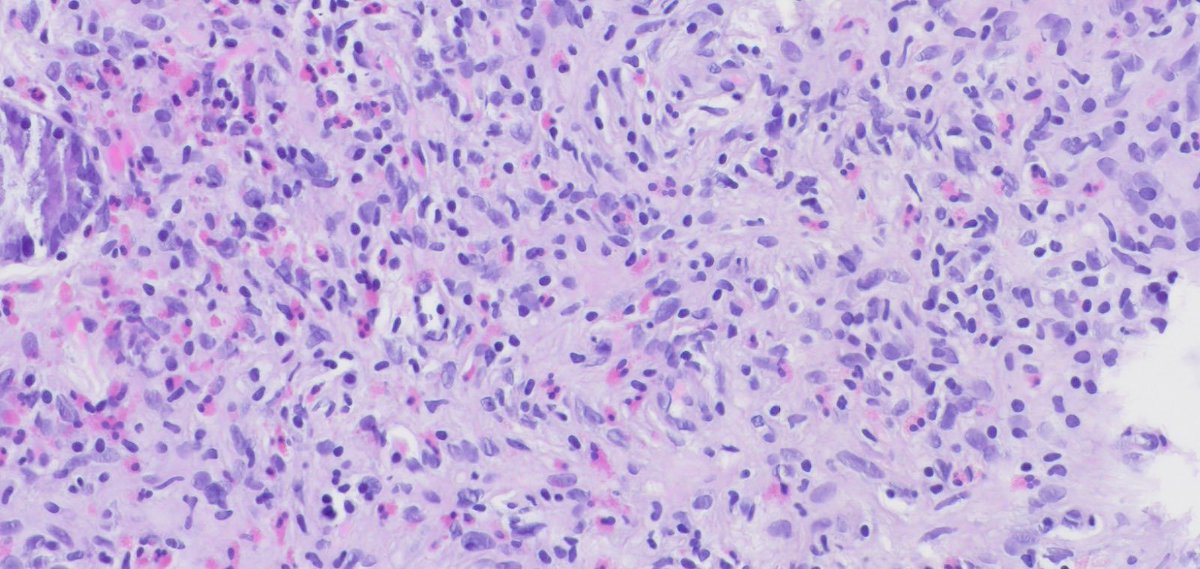

Miruna Popescu, MD

Miruna Popescu, MD@MirunaPopescu13·

Ulcerated mass in the colon. ▶️Geographic necrosis ▶️Lots of mitoses & apoptotic bodies ▶️Sheet-like & trabecular growth ▶️Highly atypical nuclei w/ prominent nucleoli ▶️Eosinophilic cytoplasm Based on 🔬H&E morphology, what is your diagnosis? #PathTwitter #GIPath

Miruna Popescu, MD tweet mediaMiruna Popescu, MD tweet mediaMiruna Popescu, MD tweet mediaMiruna Popescu, MD tweet media